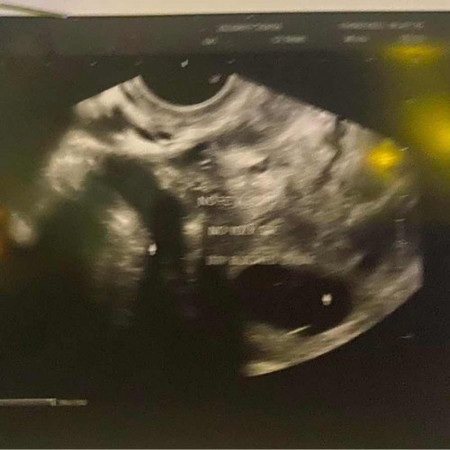

ตรวจเจอท้องลม ตอน 10วีค 5 วัน

ตรวจเจอท้องลม ควรทำยังไงต่อดีค่ะ#ขอบคุณล่วงหน้านะคะ #คุณแม่ๆช่วยแนะนำหน่อยค่ะ